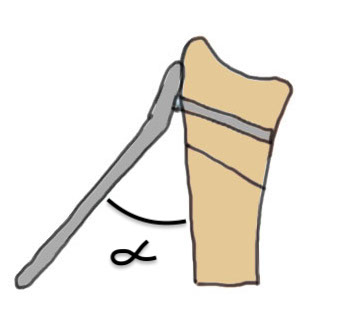

Dorsal opening wedge osteotomy

Advantage

Lengthens the distal radius

May be easier to correct in coronal and sagittal plane

Disadvantage

Dorsal approach / dorsal plate - extensor tendon issues

Technique

3 / 4 dorsal approach

- expose distal radius

- can use half pins to control distal fragment

- protect structures with homan retractors

- osteotomy with microsagittal saw

- correct radial articular surface in sagittal & coronal planes

- trapezoidal bi-cortical iliac crest autograft / synthetic graft

- dorsal locking plate